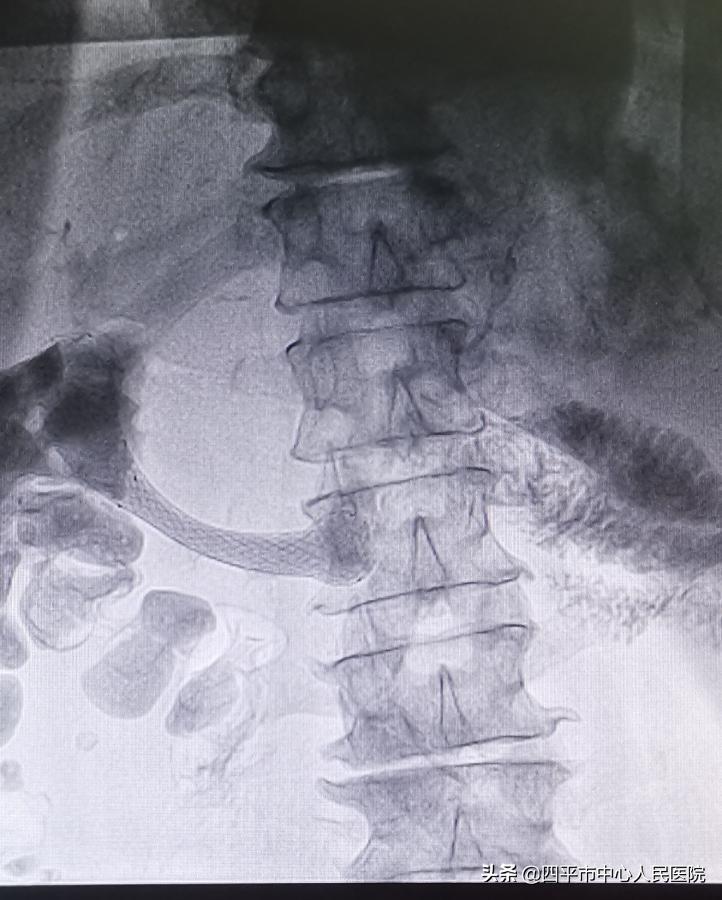

定位准确后在DSA透视下释放支架 术后造影剂通过顺畅